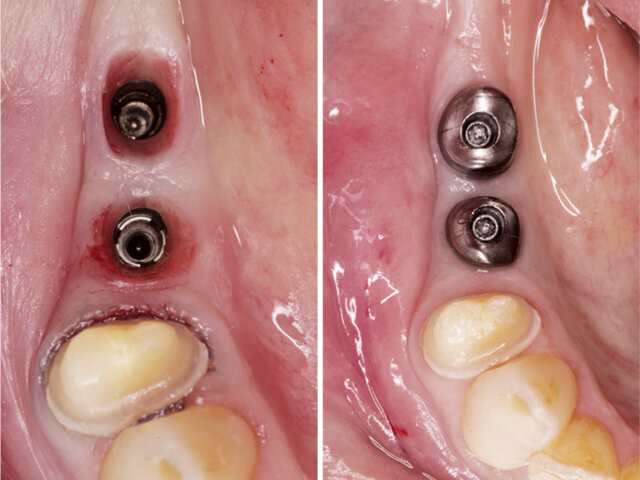

Zirlux 16+ na implantátech

CAD/CAM abutmenty a korunky vyrobené ze Zirlux 16+

Zirlux 16+ jako kotevní prvek

Díky výjimečným fyzikálním vlastnostem Zirlux 16+ je možno materiál použít na výrobu primárních částí retenčních prvků pro hybridní náhrady. Materiál Zirlux 16+ je tedy vhodný pro výrobu kotevních prvků pro hybridní náhrady. Galvanizovaná sekundární část byla intraorálně vlepena do konstrukce snímatelné části hybridní náhrady.